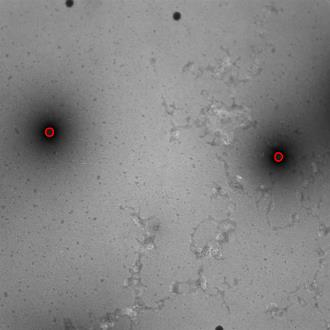

Regular monitoring of the primary particles and purity profiles of a drug product during development and manufacturing processes is essential for manufacturers to avoid product variability and contamination. Transmission electron microscopy (TEM) imaging helps manufacturers predict how changes affect particle characteristics and purity for virus-based gene therapy vector products and intermediates. Since intact particles can characterize efficacious products, it is beneficial to automate the detection of intact adenovirus against a non-intact-viral background mixed with debris, broken, and artefact particles. In the presence of such particles, detecting intact adenoviruses becomes more challenging. To overcome the challenge, due to such a presence, we developed a software tool for semi-automatic annotation and segmentation of adenoviruses and a software tool for automatic segmentation and detection of intact adenoviruses in TEM imaging systems. The developed semi-automatic tool exploited conventional image analysis techniques while the automatic tool was built based on convolutional neural networks and image analysis techniques. Our quantitative and qualitative evaluations showed outstanding true positive detection rates compared to false positive and negative rates where adenoviruses were nicely detected without mistaking them for real debris, broken adenoviruses, and/or staining artefacts.